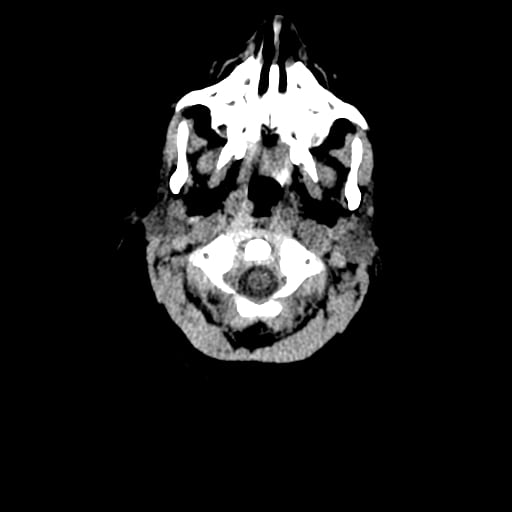

Age: 1

Sex: Male

Indication: Fall